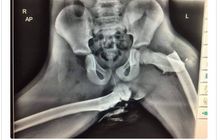

Foto X-ray Ini Buktikan Bahaya Meletakkan Kaki di Atas Dasbor Mobil

Postingan di twitter menunjukkan foto X-ray akibat dari kecelakaan di mana seorang wanita di Wales, Inggris meletakkan kaki di atas dasbor mobil.